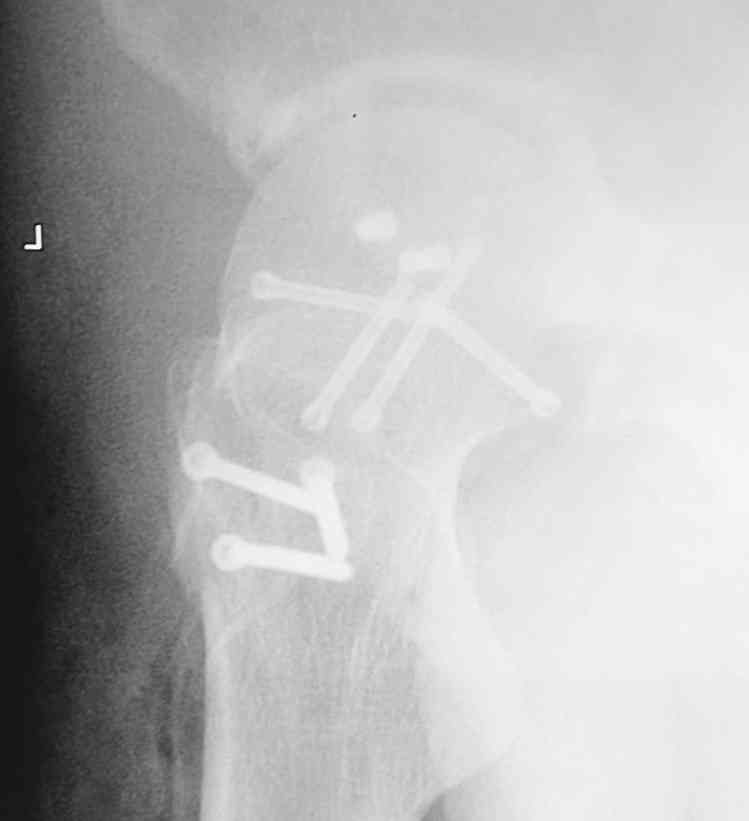

[Ortho] Pipkin II

Стоило ли заниматься остеосинтезом в этом случае?

Мужчина, 50 лет, активный, падение с высоты. При поступлении вправление

вывиха, других повреждений нет Без значимой сопутствующей патологии, не

курит. Стоило ли выполнять остеосинтез при таком оскольчатом переломе

или сразу пойти на ТНА?